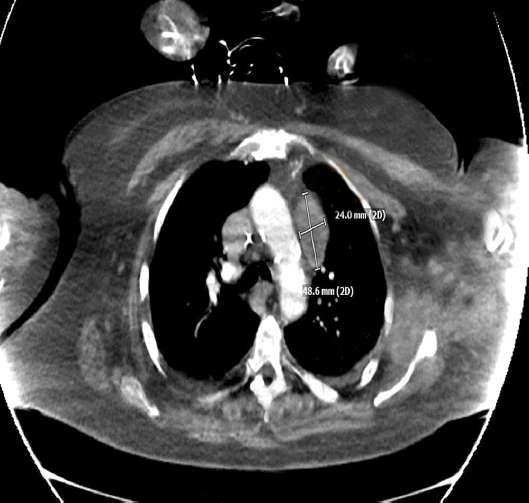

Феохромоцитома (0.1–0.6%)

Диагностика

• Пароксизмальная гипертензия или криз.

• Сердцебиение, головная боль, потливость, бледность.

• Ортостатическая гипотензия.

• Семейный анамнез феохромоцитомы.

• Признаки нейрофиброматоза на коже.

• Инциденталома надпочечника.

• Генетические аномалии (RET, VHL, SDHA, SDHB, SDHD, SDHC, SDHAF2, MAX, TMEM127, нефрофиброматоз 1 типа).

• Свободные метанефрины (неактивные продукты метилирования адреналина и норадреналина) плазмы.

• Фракционированные метанефрины (метанефрин, норметанефрин) в суточной моче (при N уровне и высокой вероятности повторить в день приступа).

• Катехоламины (эпинефрин, норэпинефрин) менее точны, но подтверждают диагноз при выраженном (>2 раз) повышении.

• Уровень катехоламинов возрастает при остром заболевании, приеме лекарств (антидепрессанты, антипсихотики, леводопа).

• Компьютерная томография с контрастированием всего забрюшинного пространства, живота и таза в случае повышенного уровня метанефринов: нативная плотность ≤10 HU инциденталомы исключает феохромоцитому.

• Магнитнорезонансная томография (режим T2) для параганглиом головы, шеи.

• Изотопное сканирование с мета-йодобензилгуанидином.

Лечение

• Альфа-блокаторы (доксазозин 1 мг однократно до 10 мг дважды по АД) ± бета-блокаторы (метопролол 25 мг однократно до 100 мг дважды, ЧСС • Лапароскопическое удаление опухоли.

• Химиотерапия.

- Феохромоцитома правого надпочечника. Степень АГ 3. ГЛЖ. Риск 4 (очень высокий).